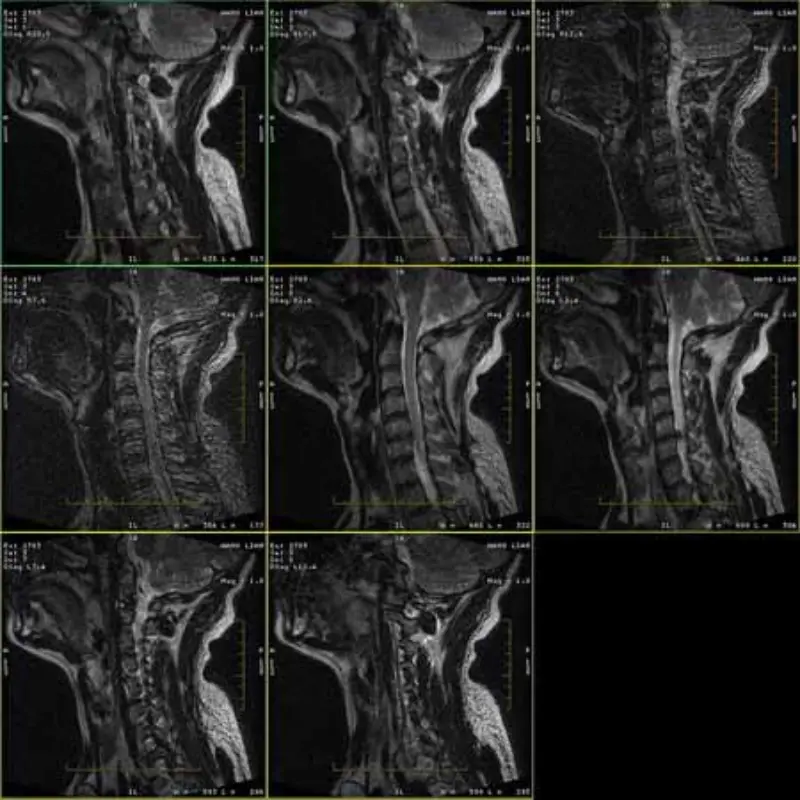

FRFSE- ja GRE-protokollien kuvissa on haamukuvia ja joskus matalan SNR-kuvat näkyvät yhdessä sarjassa. Mutta SE-protokollan kuvat ovat normaaleja.

Katso liite kuvat.